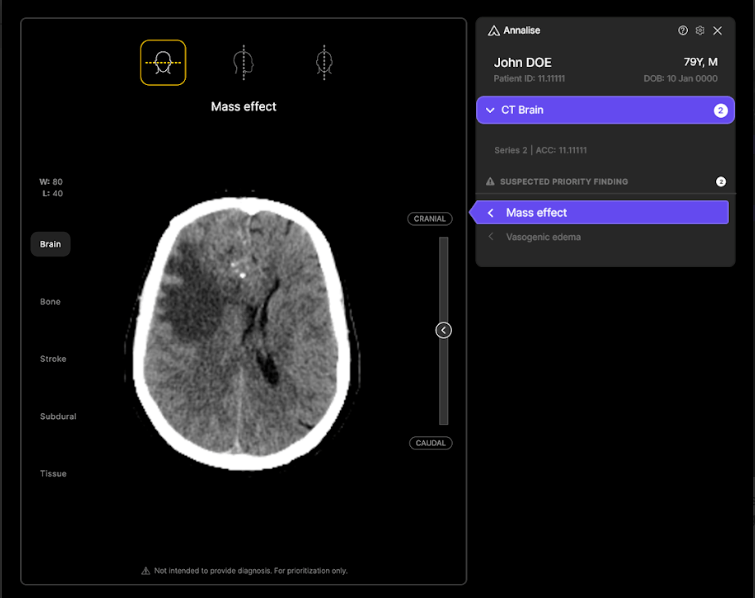

Harrison.ai offers two different products: diagnostic software that’s focused on radiology, called Annalise.ai, and a pathology-focused offering, Franklin.ai. Both have the overarching goal of helping clinicians diagnose medical conditions more accurately and efficiently. The startup believes the AI tools can aid in the early detection of medical conditions, expedite treatment decisions, and reduce wait time for patients.

It began monetizing Annalise.ai back in 2022 and has tripled contracted annual recurring revenue each year for the past three consecutive years for the radiology offering, he added. Annalise.ai is currently operational in more than 1,000 healthcare facilities in various countries, supporting the treatment of over 6 million patients annually.

Similarly, its CT Brain product has obtained regulatory clearance for the detection of up to 130 findings — again, a number that’s approximately 4x greater than that of competitors, according to Tran.